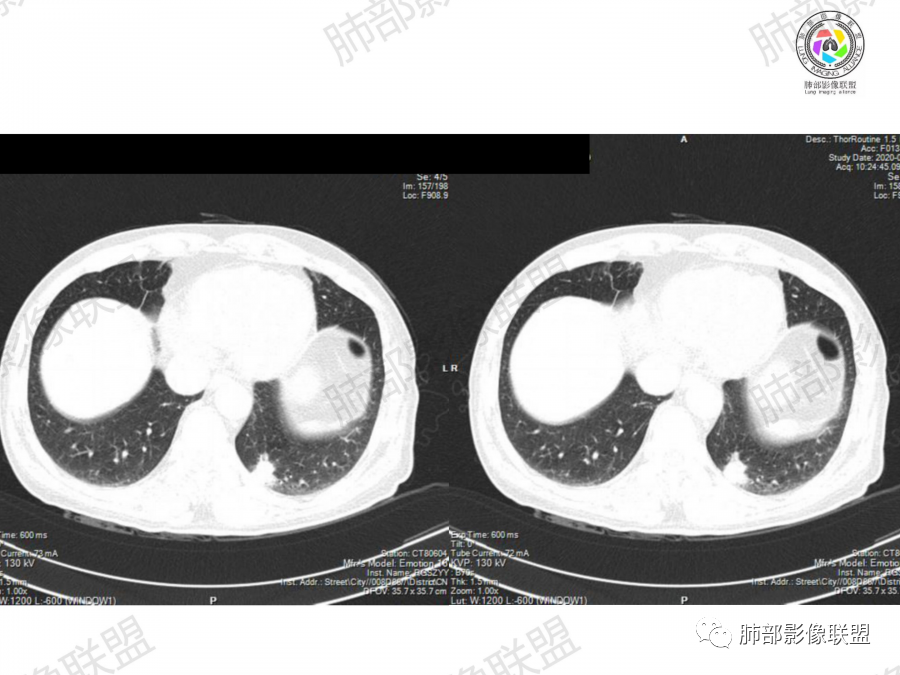

晨读:左肺下叶胸膜下实性结节影边缘毛糙,有毛刺,分叶,近段支气管未见显示,可能堵塞,远端宽基底与胸膜相贴,边缘平直,部分彭隆,病灶局限、单发,无增强,不好判断肿瘤血供,临床男性,63岁,无症状,体检发现,有吸烟史,考虑恶性:腺癌,鳞癌,小细胞肺癌,鉴别:肺隐球菌建议增强及穿刺检查。

老年男性,吸烟史。左下肺外周结节,糊墙,部分边缘平直、部分膀隆,见分叶,支气管截断?部分边缘似乎有GGO,内部情况不详。整体考虑恶性,腺癌可能性大,注意鉴别鳞癌、炎性肉芽肿。

晨读病例,老年人 ,吸烟史,左肺下叶结节影,密度均匀,边缘毛糙,周围可见长毛刺,病灶边缘分叶,局部膨隆,部分边界平直,收缩,病灶相邻胸膜处可见糊墙征象,病灶近肺门处见支气管堵塞,考虑恶性病变,周围型肺癌:鳞癌伴肺不张>腺癌,鉴别隐球,炎性假瘤。

细、长、软毛刺

边缘模糊,支气管关系不明确

糊墙,胸膜下脂肪间隙明显增厚

边缘平直为主,部分膨隆,糊墙征

密度比较均匀;

2、影像表现:无肺气肿背景、定位左肺下叶后基底段,不规则结节、与支气管关系不明确,部分边缘平直、部分膨隆,病变与胸膜宽基底相连,病变与胸膜糊墙征,病变周围见细、长、软毛刺,病变密度比较均匀。影像总体倾向炎症、符合肺组织慢性炎症伴机化。